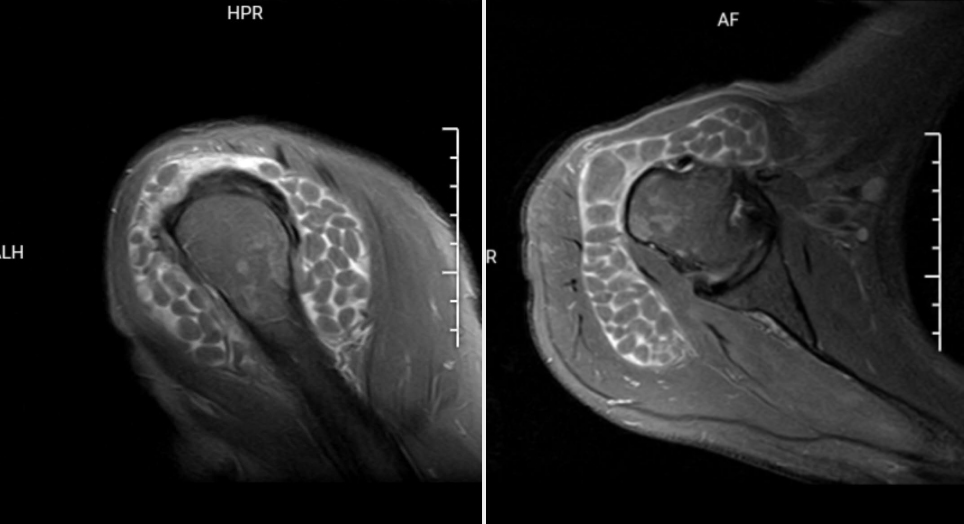

X 线检查无特殊意义,以 MRI 检查最为敏感,关节周围软组织可见不同程度水肿,肩峰下可见积液,以及大量直径不等(1 ~ 10 mm)的类圆形占位,与周围肌肉组织相比呈等 T1 稍长 T2 信号。

无明显症状的关节病,米粒体滑囊炎会被忽略漏诊。主要需与色素沉着绒毛结节性滑膜炎 (PVNS) 和滑膜软骨瘤相鉴别。鉴别诊断要点主要以 MRI 为主。

化生软骨往往呈叶状,未钙化时的 T1 像为等信号,T2 加权像为高信号;已经钙化的则 T1 和 T2 加权像均为高信号。